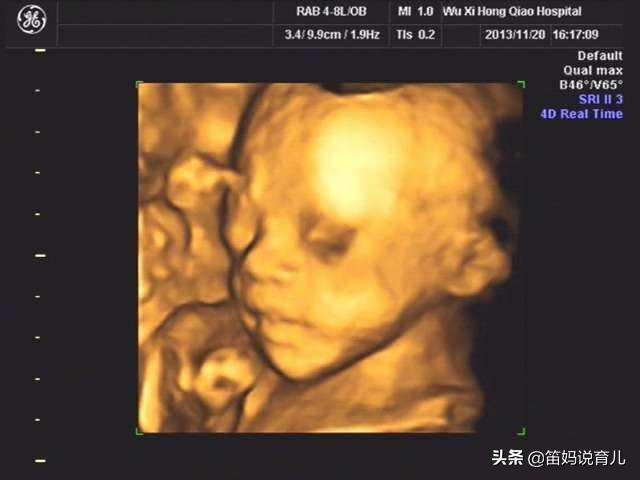

为什么有的人做四维彩超看不到胎儿的五官?

看四维报告单 , 我们会发现 , 上面关于头面部的描述中 , 只有对眼框、鼻、唇部的判定 , 没有耳朵的踪影 。

据医生介绍 , 四维彩超不负责对耳朵、脚趾、手指等部位进行排畸检查 。 但实际上耳朵是能看到的 , 我看很多四维照片上都出现了耳朵 。 负责任的医生也会帮忙看一下不在检查之列的部位 , 但不写到报告单上 。

胎儿体位影响

做四维彩超时 , 宝宝不配合 , 只给一个正面、只给一个侧面、只给一个背面 , 就看不到宝宝的耳朵 。 所以 , 就出现了医生让孕妈妈反复做四维、四维时间长的问题 。

胎儿的身体挡住了耳朵

胎儿在肚子里是经常活动的 , 手舞足蹈起来谁也控制不了 , 所以难免出现肢体挡住耳朵的情况 。 比如宝宝做出双手抱住脑袋的动作 , 这样就把耳朵生生地挡住了 , 怎么也看不到 。

还有的脐带也会挡住宝宝的耳朵 , 所以也有可能看不到 。 如果想看到耳朵就和医生好好说一下 , 或者再做一次 。

耳朵紧贴头部

不知注意到没有 , 孩子出生后 , 耳朵是紧贴在头部的 , 到十几天后才会慢慢舒展开 。 在做四维的时候 , 耳朵也是紧贴在头部的 。 这时候耳朵很小 , 宝宝的头部侧面也不是很规则 , 耳朵就不容易分辨 , 所以是看不清楚的 。

所以 , 医院里有一项规定 , 像耳朵、手指、脚趾这些容易出现误差的部位 , 是不负责判断的 。

总之 , 做四维彩超看不到耳朵的情况是很多的 , 不用担心 , 这种情况的不在少数 。 等宝宝长大一点 , 再去做彩超就会看得更清楚一些 。